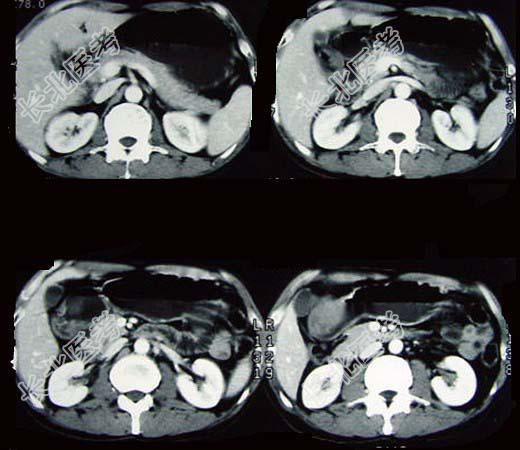

- 单项选择题女性,42岁, 腹痛、黑便1周,CT扫描见胃窦部圆形块影, 最佳的诊断是  (    )